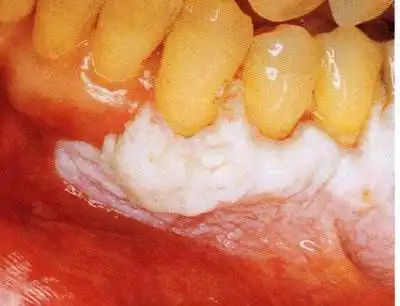

[图片资料]口腔粘膜病图谱→白斑的临床表现(一)(转载) - 口腔专业